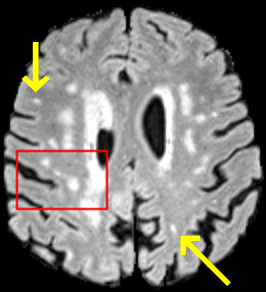

To test the impact of the iterative refinement on YODA’s translation quality, we compared regression and diffusion sampling on the RS data and present additional generation examples in Fig. 6. We observe that diffusion sampling visually resembles the appearance of the acquired images. Regression sampling preserves key anatomical features – the GM/WM boundary, WMHs (Fig. 4), the outline of the pallidum (Fig. 6) – but omits many high-frequency features. To investigate whether iterative refinement during diffusion sampling adds relevant and systematic medical information or only imitates acquisition noise, we performed ExpA sampling, i.e. averaging the output of several ( or ) diffusion trajectories. We observed a gradual loss of high-frequency details when increasing the (see also the supplementary video), indicating that the effect of the iterative refinement is non-systematic. For , the images are visually almost indistinguishable from the initial regression solution (see the supplementary video, and Fig.4 and 6). We directly compared the synthesis results of ExpA () and regression sampling quantitatively and found the differences to be minimal (SSIM: 99.73%, PSNR: 45.30 dB), i.e. diffusion sampling approaches the initial regression solution for a high . The quantitative analysis of the image quality (Tab. 1) showed that diffusion sampling impairs the assessed SSIM and PSNR in comparison to regression sampling for both the in- and external test sets, which we attribute to noise generation (Sec. 3.1). In turn, ExpA averages improved both metrics and, for , performed mostly on par with the regression solution in both test sets in terms of SSIM, while the PSNR in the RS was slightly increased (Tab. 1). However, we observed that ExpA sampling YODA improves the replication of systematic 3D low-frequency image intensity drifts (bias fields) due to the 3D synchronization in 2.5D diffusion sampling. Yet, this apparent advantage did not generalize to the external MBB dataset, as bias fields are MR protocol-specific.

On the RS data (Tab. 1), regression sampling of YODA significantly outperformed all competing methods both w.r.t. the image quality and – except the ALVR for MADM – downstream WMH segmentation, whereas the DB of Choo et al. [31] achieved an higher WMH CNR.

When analyzing the RS synthesis results (Fig. 4), we noted that most reference methods strive to imitate realistic images, but several artifacts can be observed such as hallucinated WMHs (SynDiff) and salt-and-pepper noise (SynDiff, I2I-Mamba, ResViT).

However, SelfRDB [29], and, especially, MADM [35] and the DB of Choo et al. [31] generate very smooth images (Fig. 4) with an high FID, i.e. low perceptual realism.